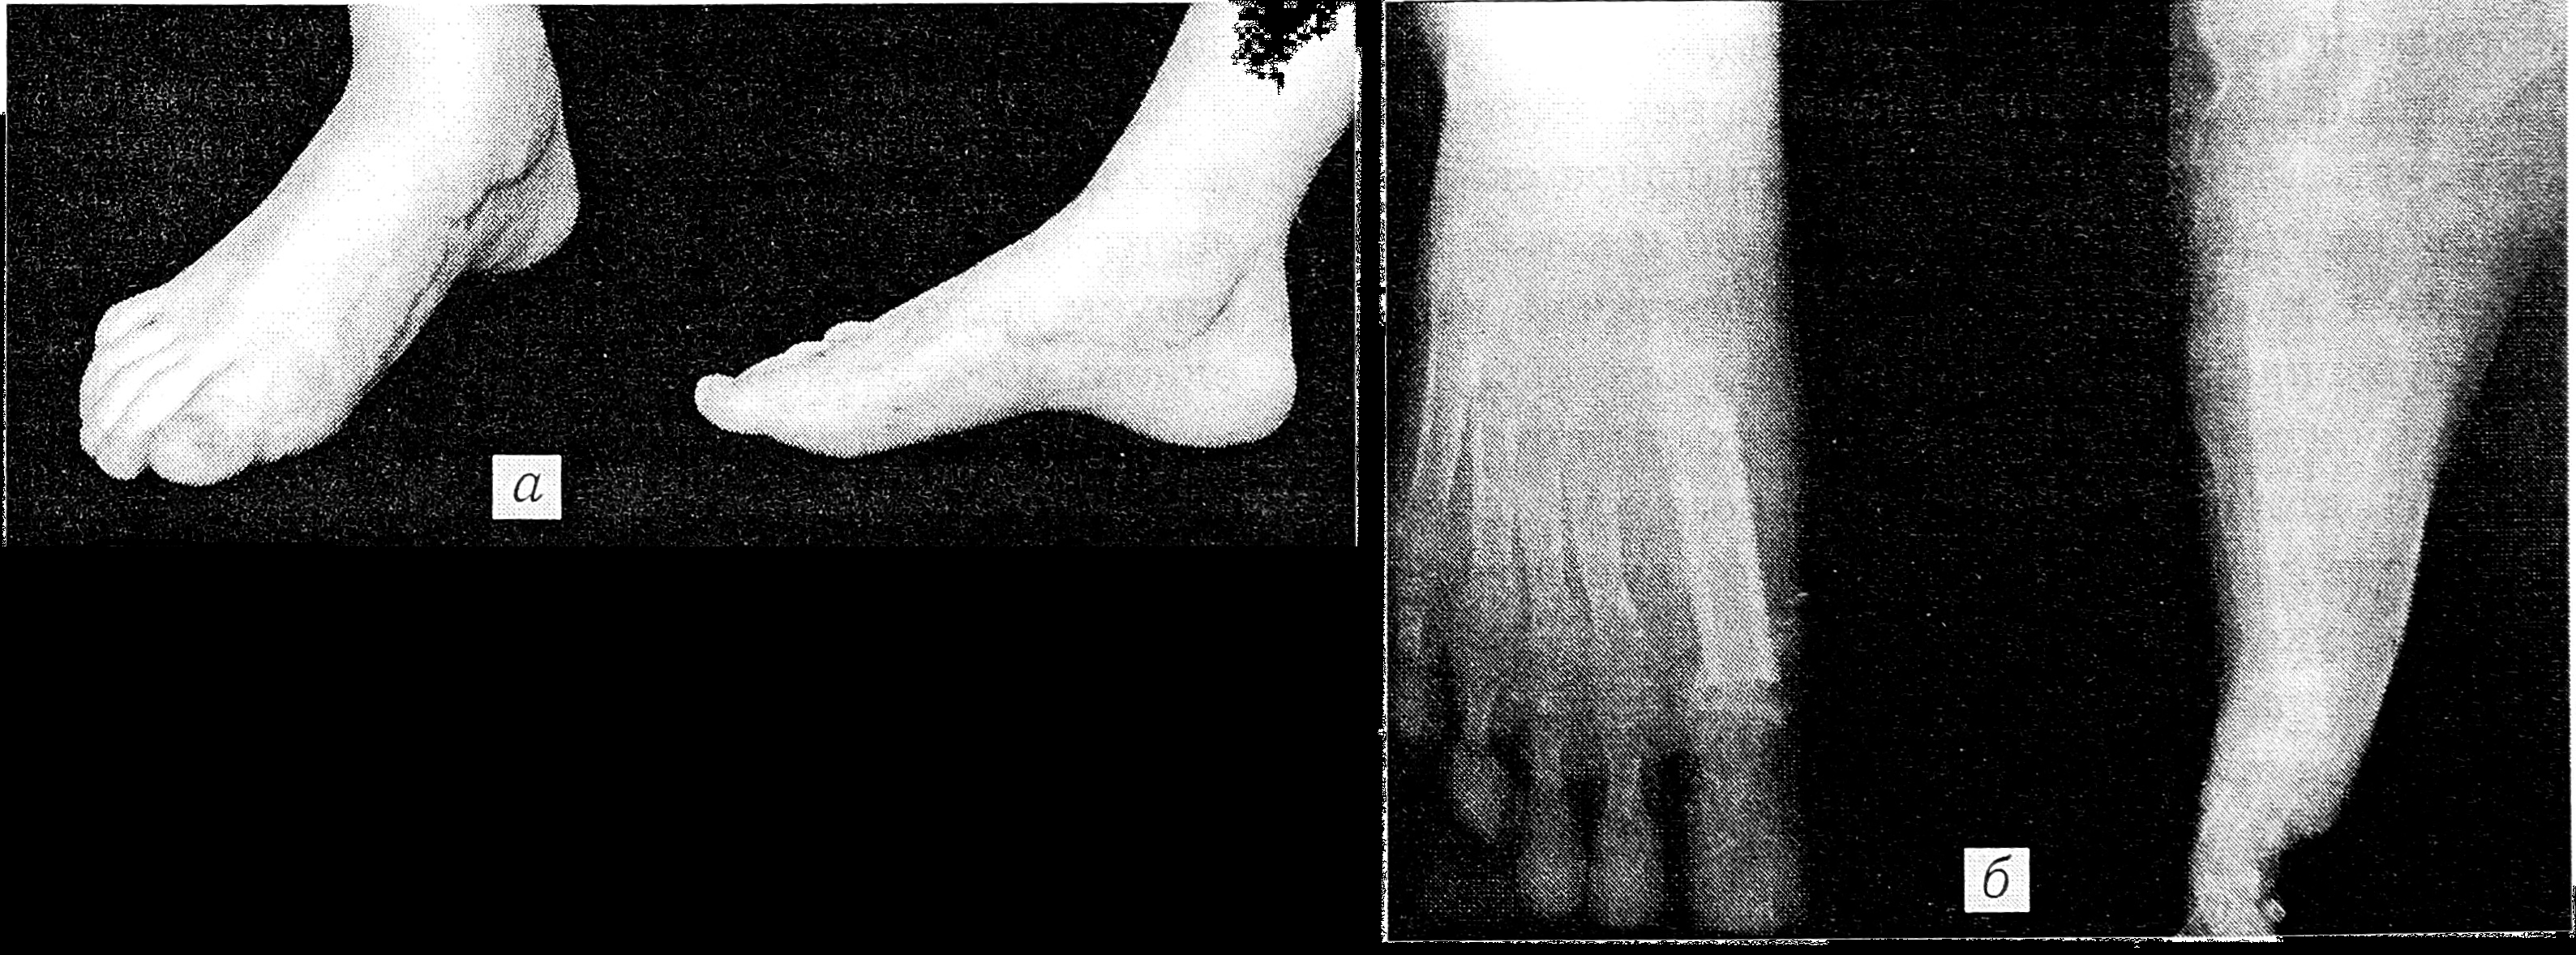

Больная К., 13 лет, поступила в ЦИТО по поводу тотального дефекта I плюсневой кости правой стопы вследствие посттравматического остеомиелита и неоднократных секвестрэктомий, с жалобами на затрудненную ходьбу и нарастающую деформацию I пальца (рис. 1). Первым этапом на I луч стопы был наложен стержневой компрессионно-дистракционный аппарат, с помощью которого создан диастаз на длину пястной кости между клиновидной костью и основной фалангой пальца (рис. 2). После этого 19.09.95 под общим обезболиванием двумя бригадами хирургов произведены замещение дефекта плюсневой кости свободным васкуляризированным малоберцовым трансплантатом, эндопротезирование плюснефалангового сустава силиконовым эндопротезом, пластика дефекта кожи полнослойным кожным трансплантатом (рис. 3). Одна бригада хирургов иссекла рубцы по внутренней поверхности стопы, выделила для наложения микрососудистых анастомозов заднюю большеберцовую артерию и сопровождающие ее вены, подготовила ложе для костного трансплантата. Вторая бригада в это время производила забор малоберцового костного трансплантата длиной 9,5 см с питающей его артерией и венами, мышечной муфтой толщиной 0,8 см. Затем костный трансплантат был адаптирован на стопе и фиксирован к соседним костям спицами Киршнера (рис. 4). Перед выполнением остеосинтеза на дистальный конец трансплантата был «надет» соответствующего размера силиконовый эндопротез, предназначенный для замещения головки плюсневой кости. Наложены микроанастомозы между артерией костного трансплантата и задней большеберцовой артерией и сопровождающими их венами. После снятия сосудистых клипсов отмечено обильное капиллярное кровотечение из мышечной муфты, свидетельствующее о хорошей проходимости сосудистых микроанастомозов и кровообращении в трансплантате. (Последнее было многократно подтверждено в разные сроки послеоперационного периода допплерографически.) На рану наложены послойные швы. Оставшийся кожный дефект размером 1,2 × 4 см закрыт полнослойным кожным аутотрансплантатом. Наложены асептическая повязка и задняя гипсовая лонгета с фиксацией стопы в положении, исключающем малейшее натяжение микрососудистых анастомозов.

Рис. 1. Рентгенограммы стоп больной К. при поступлении: видны тотальный дефект I плюсневой кости правой стопы и деформация ее пальцев.

Послеоперационное течение гладкое. Движения в плюснефаланговом суставе начаты через 2,5 нед, через 8 нед удалены спицы и разрешена нагрузка на стопу. При осмотре через 8 мес после операции форма стопы правильная (рис. 5, а), больная ходит в обычной обуви, не хромая, занимается в танцевальной школе. После большой нагрузки отмечает незначительные боли в области плюснефалангового сустава. Движения в нем в пределах 15°. На рентгенограмме (рис. 5, б) структура трансплантата обычная для этих сроков при данном виде костной пластики, имеется деформация проксимального суставного конца основной фаланги I пальца стопы, чем можно объяснить боли в этой области при большой нагрузке.

Рис. 5. Через 8 мес после операции.

a — внешний вид стопы; б — рентгенограммы: остеопороза трансплантата, указывающего на его резорбцию и замещение новообразованной костной тканью, нет, имеется деформация проксимального суставного конца основной фаланги I пальца.